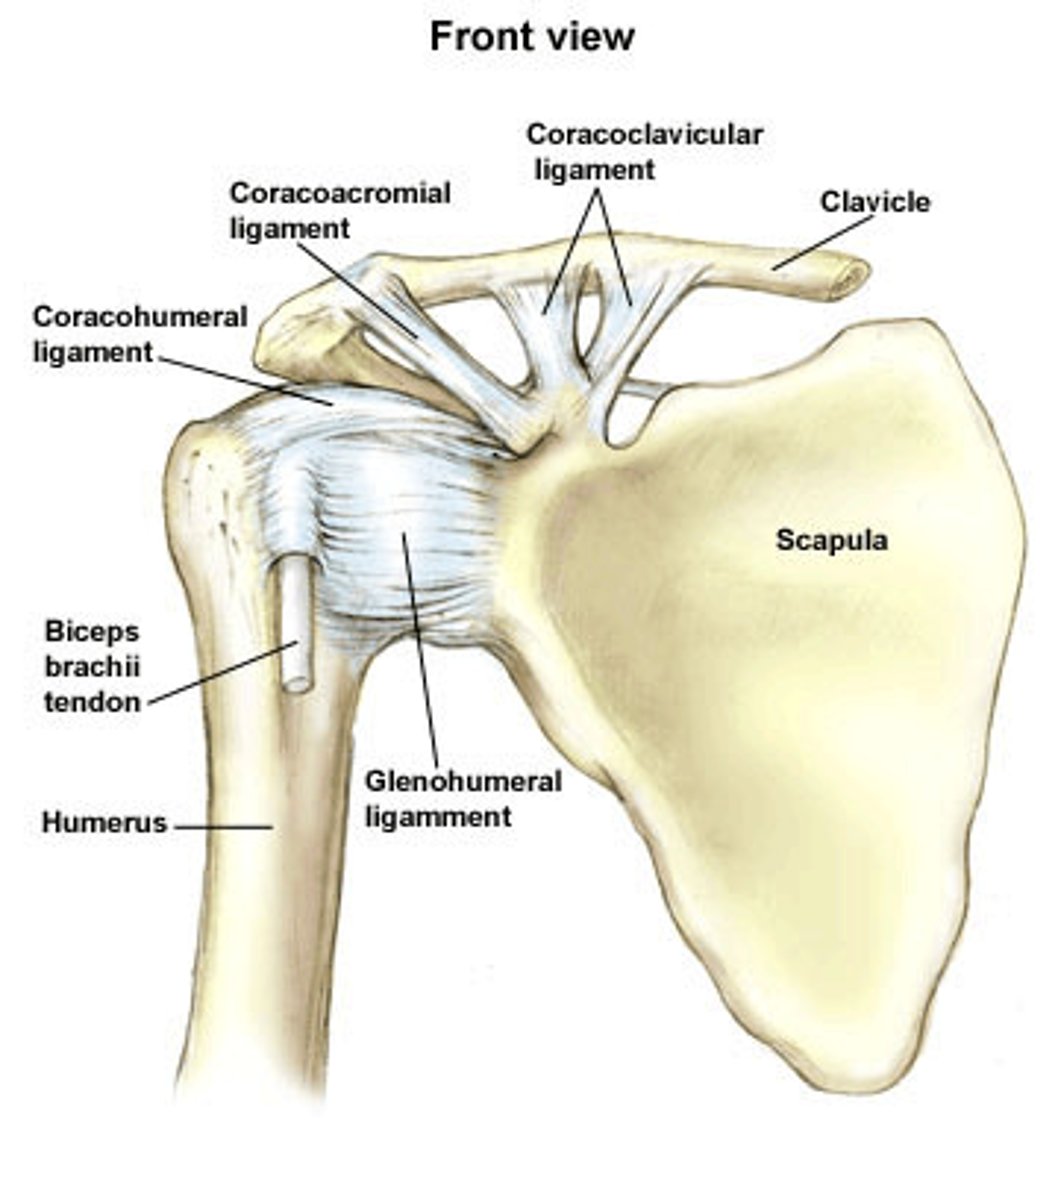

coracohumeral ligament

glenohumeral ligament

What is the shoulder joint reinforced by?

4 rotator cuff tendons

Acromioclavicular ligament